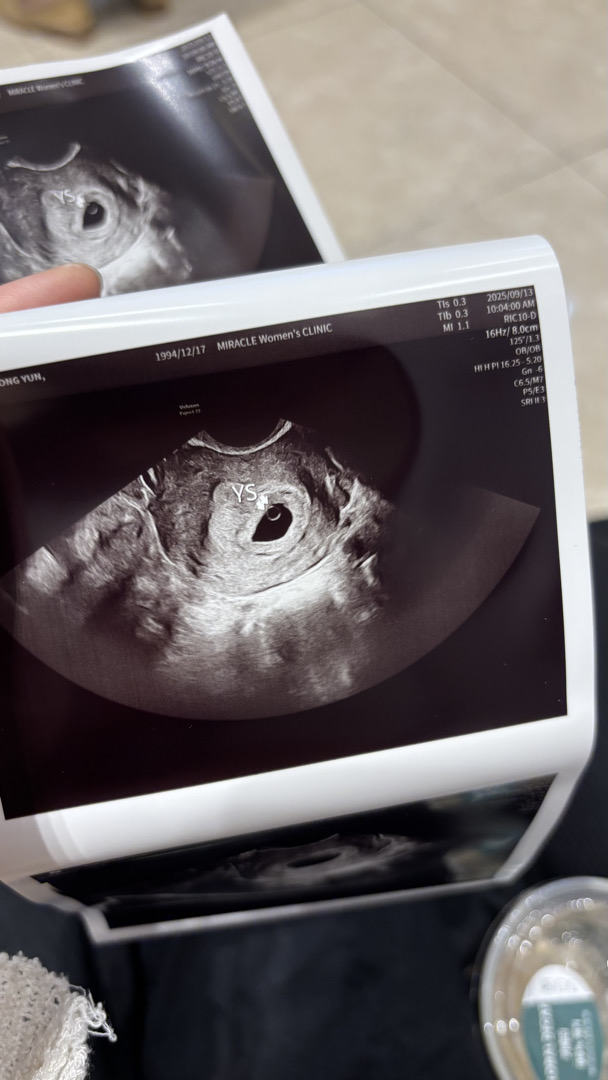

오늘 아기집들이 다녀왔오요!

위치랑 난황까지 100점이래요!! ㅠㅠ! 그치만 이젠 또 심장소리듣기전까지 덜덜입니다 막생 8월 5일 예상주차 5주 4일차에요!

앗 축하드려요!! 미라클 촘파사진 넘 선명해서 좋아여😆